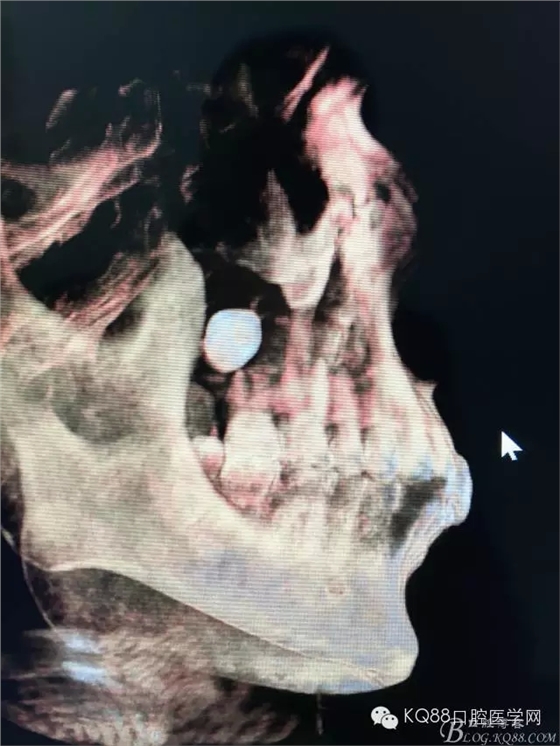

圖5. 右側(cè)三維側(cè)面觀:18位于竇腔內(nèi)。上頜竇后份的頰側(cè)骨壁完全破壞消失。